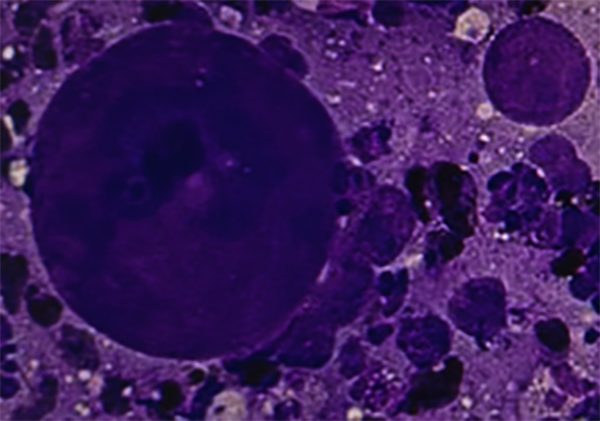

呼吸与危重症医学科(三)缪雨青主治医师即刻开展ROSE检测,快速病理当场便发现了异常细胞!

术后周老伯生命体征平稳,未出现出血、气胸等并发症,最终病理确诊为肺腺癌。依托这份精准的病理报告,肿瘤科团队迅速为周老伯量身定制个体化治疗方案。